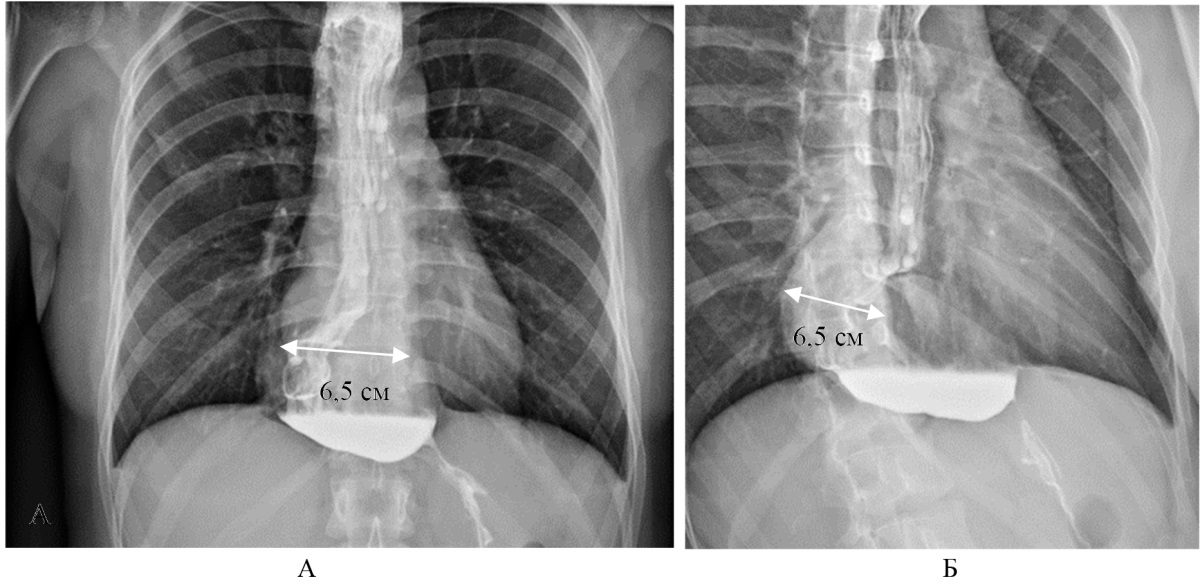

Рентгеноскопия с контрастным веществом (от 04.03.2024): пищевод расширен в верхней, средней и нижней трети до 6,5 см в диаметре (рис. 3 А, Б). Терминальный отдел пищевода сужен до 0,2 см в диаметре. Эвакуация контраста резко замедлена, одной малой порцией на протяжении всего исследования. Заключение: рентген-признаки ахалазии кардии III ст.

Рис. 3. Больная Т. Рентгеноскопия расширенного пищевода: А — проекция спереди; Б — проекция сбоку

Примечание: фотографии выполнены авторами.

Fig. 3. Patient T. Fluoroscopy of the dilated esophagus: А — front view; Б — side view